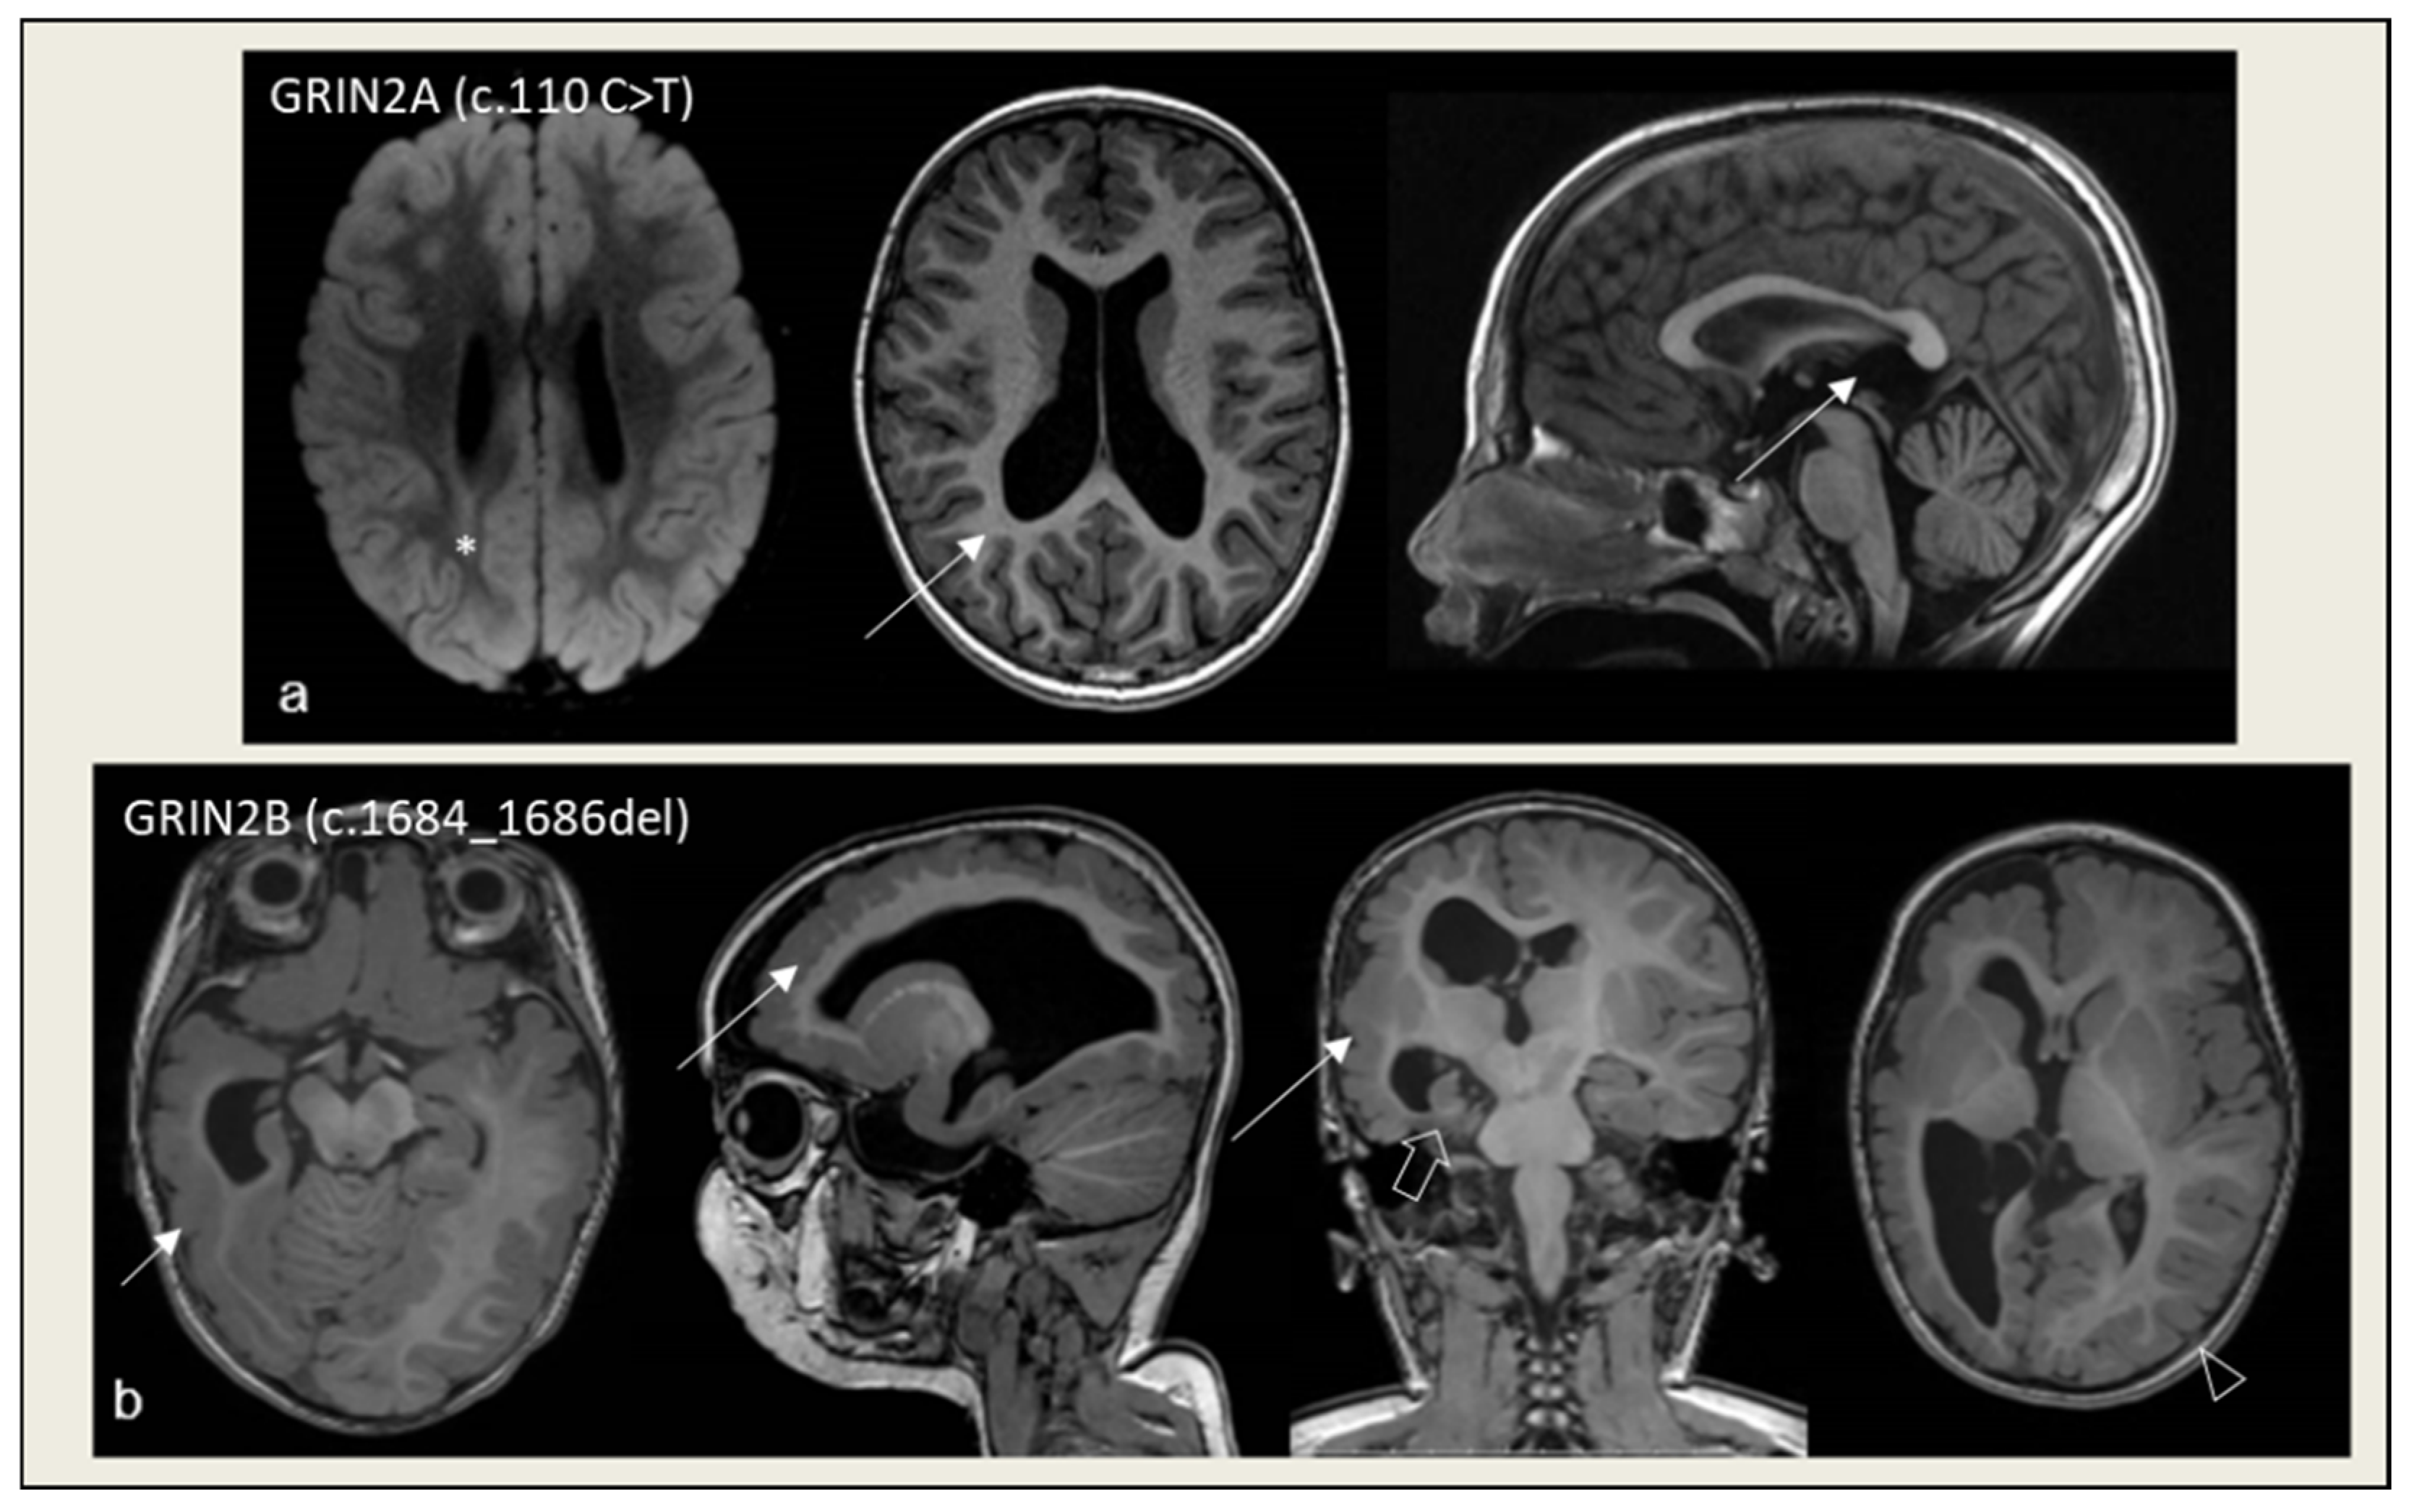

- Avsenik, J.; Benedik, M.P.; Rogač, M.; Biswas, A.; Sudhakar, S.; D’Arco, F.; Löbel, U.; Mankad, K. Divergent Presentation of GRIN2B Neurodevelopmental Disorder in Monozygotic Twins: Case Report with Unique Imaging Phenotypes. Neuropediatrics 2025, 56, 269–273. [Google Scholar] [CrossRef]

- Brock, S.; Laquerriere, A.; Marguet, F.; Myers, S.J.; Hongjie, Y.; Baralle, D.; Vanderhasselt, T.; Stouffs, K.; Keymolen, K.; Kim, S.; et al. Overlapping Cortical Malformations in Patients with Pathogenic Variants in GRIN1 and GRIN2B. J. Med. Genet. 2023, 60, 183–192. [Google Scholar] [CrossRef]

- Smigiel, R.; Kostrzewa, G.; Kosinska, J.; Pollak, A.; Stawinski, P.; Szmida, E.; Bloch, M.; Szymanska, K.; Karpinski, P.; Sasiadek, M.M.; et al. Further Evidence for GRIN2B Mutation as the Cause of Severe Epileptic Encephalopathy. Am. J. Med. Genet. A 2016, 170, 3265–3270. [Google Scholar] [CrossRef]